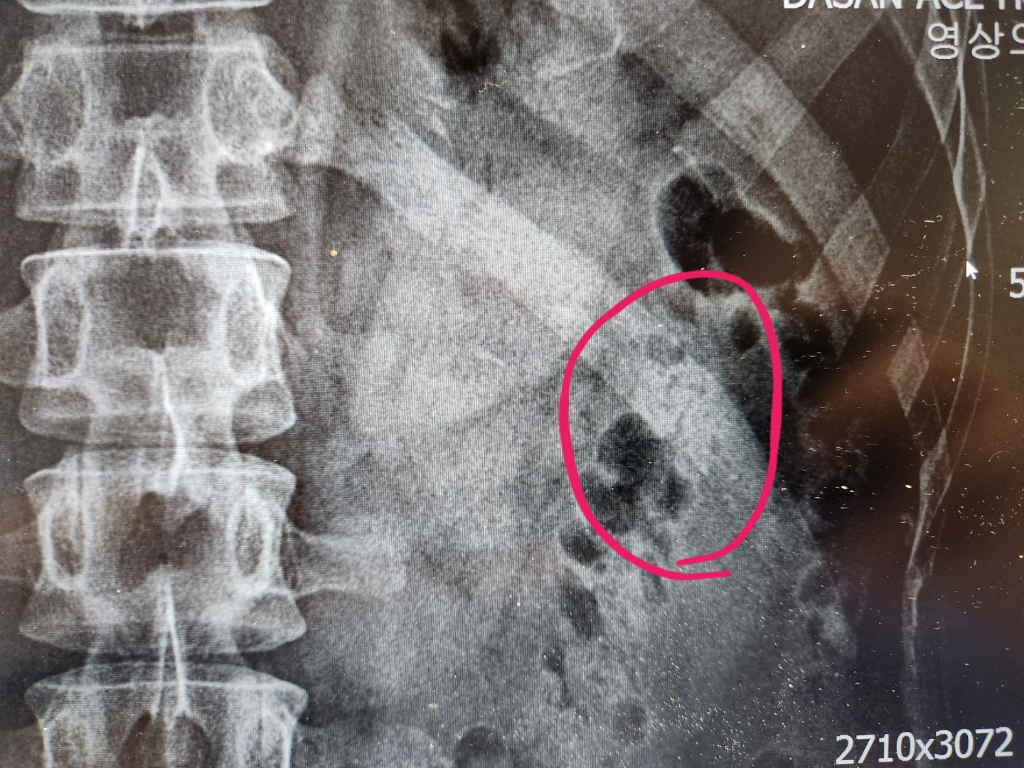

영상자료를 cd로 받아와서 직접 봤는데 제눈에도 보이는데 이게 골절이 아닌가요..?

사진의 소견을 통해서 보았을 때에 좌측의 12번 갈비뼈의 골절이 굉장히 의심스런 선이 보입니다. 해당 부위의 증상이나 엑스레이 소견으로 볼 때에 충분히 골절이라고 볼 수 있습니다. 한방은 전문성이 떨어지기 때문에 흉부외과적으로 진료를 보시는 쪽을 더 권고드립니다. 다만 갈비뼈 골절에 대해서는 스스로 붙을 때까지 추가적인 손상을 예방하고 환부를 쉬어주는 것이 최선의 치료법이기 때문에 병원에 가신다고 하여 특별한 것이 있지는 않을 것이며 진통제를 복용하며 경과를 지켜보는 것이 현재로서는 적절한 치료법입니다.

골절 가능성 있어보이나

복부 가스에 의해서도 보일수 있습니다

자세한것은 영상의학과 판독내용을 참고하시는게 좋을것 같고

병원 내에서 판독이 어려우시다면 ct 촬영한 cd을 가지고

흉부외과나 다른 병원에 가셔서 문의를 하는 것도 좋을것 같습니다.